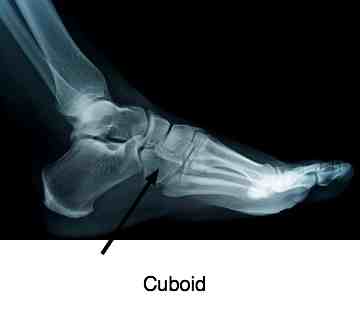

What they could not have known at the time was that the force of the blow to her little toe drove the metatarsals smack up against the Cuboid bone in her foot.The little toe had healed fine, but she could hardly walk. What made her tearful was her doctor was completely nonplussed offering only more painkillers.

I'm not knocking him - I would have reacted in the same way faced with a case of pancreatitis or an acute appendix. He was just out of his depth, not knowing too much about Cuboid bones. What made it worse was the pain started radiating up into her calf, and her odd gait had given her a terrible headache, something she hardly ever suffers from.

Fortunately it's a story that

ends well. Unless the bone is actually bruised, a fixated Cuboid

responds remarkably well to Chiropractic. After only three treatments

yesterday she declared that it's 75% better, and she could walk quite

normally. The headache lifted after the first treatment of her foot. Should the diagnosis of Chiropractic Headache include an examination of the foot? Yes sir!